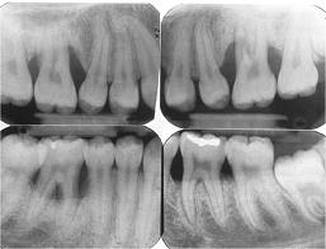

Screening. Early diagnosis of aggressive periodontitis is important as it can cause rapid permanent destruction of the periodontal tissues. It is essential that all patients undergo a routine periodontal examination to screen for any form of periodontal disease during a dental checkup.

The diagnostic tests for Localized Aggressive Periodontitis (LAP) may involve the following: